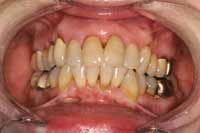

A 57-year-old woman presented with the chief complaints of jaw joint clicking and popping, jaw joint pain, and headaches. She felt that she had a bad bite and that her mouth did not close properly. Further, she disliked the appearance of her teeth. An initial screening examination revealed that she had been involved in an accident and suffered a traumatic blow to the mandible. She had a hard time closing her mouth together for several weeks following the accident. The patient stated that her jaw joints were sore on awakening. She was aware of daytime and nighttime clenching, and her jaw popped on opening and closing. She had several old fillings and crowns, and her teeth were becoming sensitive. She did not like the way her teeth looked and wanted to be happy with her smile (Figure 1 and Figure 2). The patient was given a consult to take diagnostic records.

Figure 1

The patient was unhappy with the esthetics of her smile. Note the uphill cant to the left.

Figure 2

Several occlusal flags included crowded anteriors and abfractions.